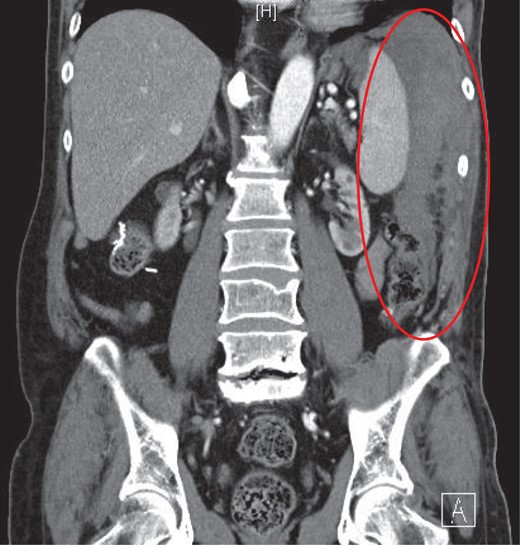

CT coronal with intravenous contrast demonstrating intraperitoneal blood products within the perisplenic region and left paracolic gutter.